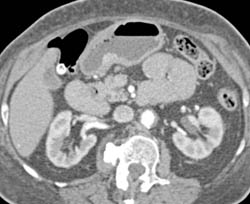

GIST Tumor